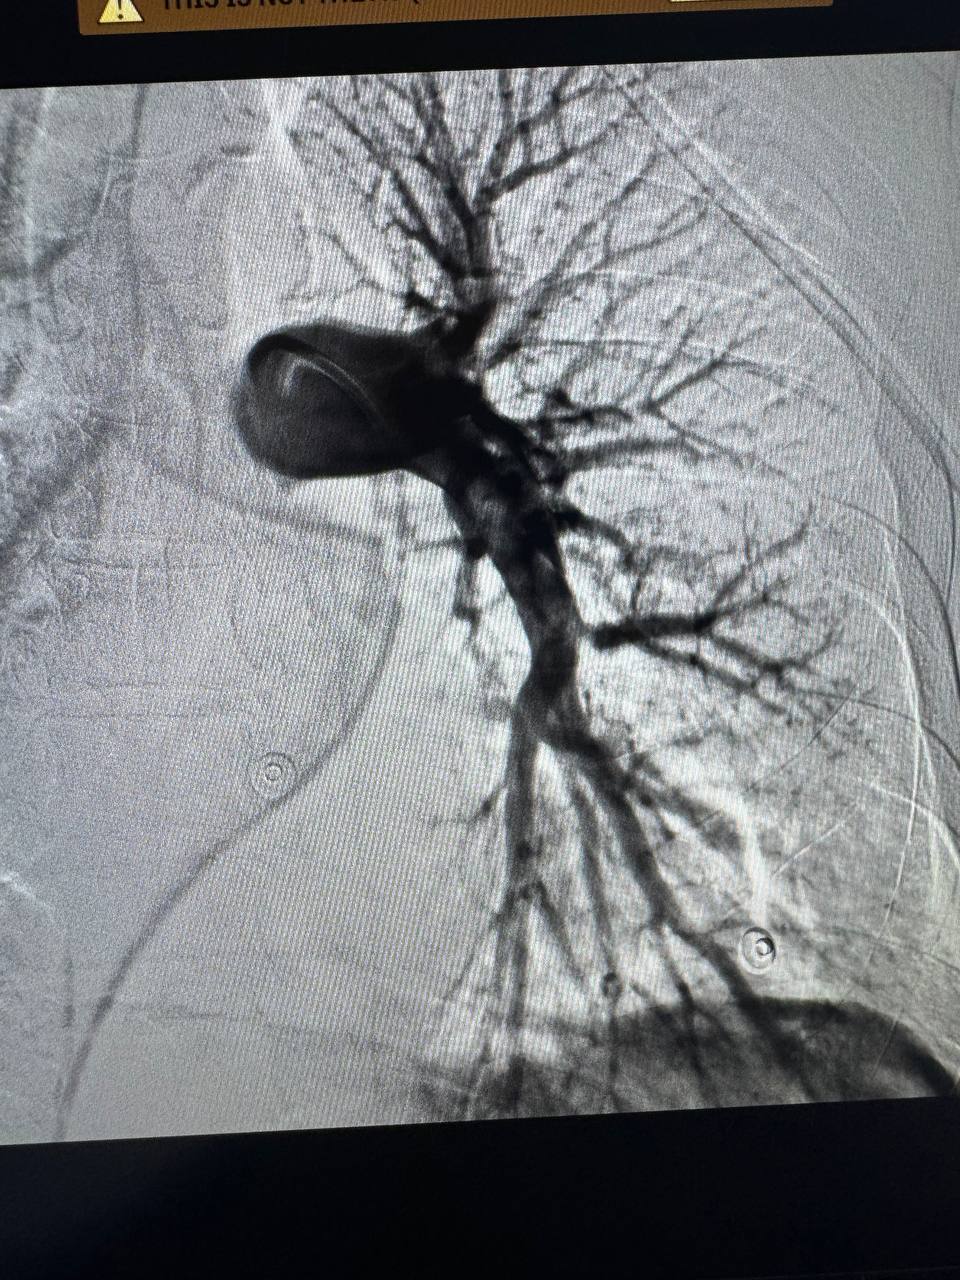

Команда медиків вирішила виконати ендоваскулярну тромбаспірацію — сучасне малоінвазивне втручання, яке дозволяє механічно видалити тромб без відкритої операції.

Під рентген-контролем фахівці ввели катетер у судину, дісталися до тромбів і успішно видалили їх за допомогою спеціальної аспіраційної системи. При цьому пацієнт був при тямі і спілкувався з лікарями.